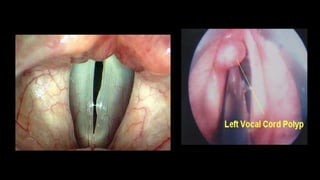

VOCAL FOLD POLYPS

•Benign swelling > 3 mm that arise from free edge of

vocal fold

•Unilateral or bilateral lesions

•Typically exophytic lesions

•Associated with vocal fold haemorrhage

ETIOPATHOGENESIS

•ETIOLOGY- Intermittent voice abuse, sudden shouting,

aspirin

•PATHOGENESIS- Vocal exertion Shearing forces

act on capillaries of mucosa capillary rupture

•Extravasation of blood focal accumulation of blood

hemorrhagic polyp

SYMPTOMS

•Abrupt onset of hoarseness during extreme vocal effort

•Intermittent subtle aberrant sounds

•Impaired falsetto register

•Chronic vocal huskiness

CLINICAL FEATURES

•Unilateral

•At the junction of anterior one thirds and posterior two

thirds of free edge of vocal cords

•May appear dark & blood filled in early stages

•May become pedunculated- moving in and out of the

glottis with inspiration and expiration

MANAGEMENT

•Microlaryngeal precise excision

•Speech therapy